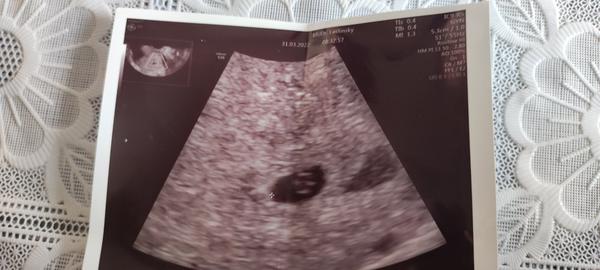

Som v 7tt a zacala som mat krce a silno krvacat , vcera vyslo zo mna sj zrazeniny krvi, bola som stym vcera na pohotovosti, vyzeralo to na portrat. Dr ma vysetril,potrat som nemala zatial , medal mi nic , poslal ma domov .Dneska mam stale bolesti a krvacam , cely den lezim

@lucia7933 ahoj, potrat moze spustit aj krvacajuci hematom.

Ak je hematom blizko (zdraveho) plodu a zacne krvacat, moze spolu so sebou strhnut aj zdravy plod=hematom ako pricina potratu. Preto ak sa nasadia lieky, hematom sa vylieci a vstrebe a zena nemusi potratit.

Mne sa to konkretne takmer stalo, na stastie mi nakoniec predpisali progesteron, predpisuje sa to bezne. A ak je plod poskodeny, tak odide bez ohladu na lieky ako pises, priroda.

@tdominika ja som ten svoj nevidela na snimke. Mne dali utrogestan a ten krasne zabral. Povedal mi lekar, ze Duphaston je slaby. Utros som brala 3x denne do cca 21tt🤔🥴 a vylozene nohy + ascorutin, minimalny pohyb a namaha, robila som z HO. Do cca 5 dni po krvacani a spineni ani stopy. Brala som to aj dalej, hematom sa uplne stratil-kontrolne uzv robili. Bejby vyzera aj na kontrolach aj prenatalnych skriningoch zdrave a ok, finale mam mat za par tyzdnov.